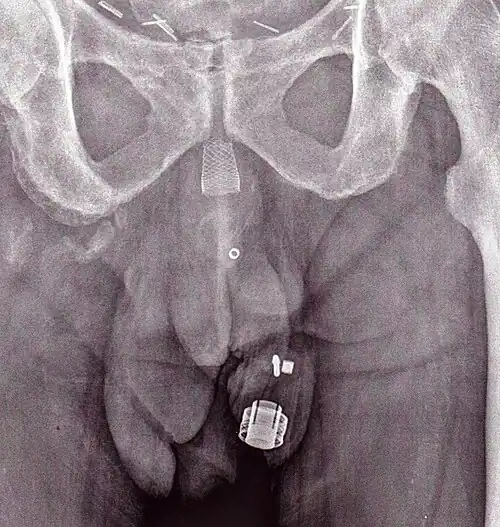

-

An X-ray image of implanted ZSI 375. The device is deactivated – the spring is compressed below the top of the cylinder. Patient is incontinent. -